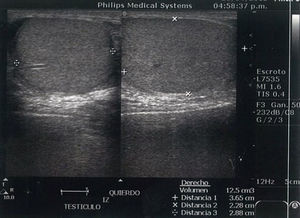

Caso clínicoAcude al servicio de urgencia del Hospital Regional de Alta Especialidad Dr. Gustavo A. Rovirosa Pérez un varón de 15 años de edad, sin antecedentes de importancia. Inició su padecimiento al presentar dolor súbito y continuo en testículo izquierdo, progresivo, con irradiación a la región abdominal e inguinal izquierda, acompañado de náuseas y vómitos, con más de 12 h de evolución a su llegada. En la exploración física, se encontró testículo izquierdo con aumento de volumen en comparación con el contralateral, doloroso, con aumento de la temperatura local, con signo de Prehn positivo, el cual consiste en mejoría del dolor al elevar el testículo afectado, además de ausencia del reflejo cremasteriano (fig. 1).

Los estudios de laboratorio únicamente con leucocitosis. El ultrasonido doppler testicular reportó cambios sugestivos de torsión testicular (figs. 1–3). Se realizó tratamiento quirúrgico de urgencia el mismo día de su admisión. Los hallazgos fueron un testículo izquierdo necrótico, con rotación de 360° del cordón espermático (fig. 4), por lo cual se realizó orquiectomía izquierda. El estudio histopatológico reportó infarto hemorrágico testicular. Durante la convalecencia no presentó complicaciones y fue egresado al día siguiente de su tratamiento quirúrgico.

La exploración física tiene un papel importante en el diagnóstico de la torsión testicular. Rabinowitz et al.7, en un estudio de 245 niños con escroto agudo, observaron una correlación del 100% entre la presencia del reflejo cremasteriano y la ausencia de torsión testicular, y concluyeron que la presencia del reflejo cremasteriano es el hallazgo clínico más valioso para descartar torsión testicular y su ausencia aumenta la sospecha diagnóstica. El estudio de imagen utilizado en nuestro medio para confirmar el diagnóstico fue el ultrasonido doppler, el cual tiene una sensibilidad del 96.8%, especificidad del 97.8%, un valor predictivo positivo del 92.3% y un valor predictivo negativo del 99.1%. Con esto se concluyó que la evaluación clínica, aunada al ultrasonido doppler, es una técnica fiable para la identificación de la torsión testicular8. Estas 2 herramientas fueron las que nos llevaron al diagnóstico de la enfermedad de nuestro caso aquí presentado. Si existe una alta sospecha de torsión testicular, a pesar de que la historia clínica, el examen físico, así como los estudios de imagen sean normales, se recomienda realizar exploración quirúrgica, con el fin de evitar la complicación más significativa como es la pérdida de testicular9. El desenlace de nuestro caso no fue la deseada, ya que el paciente se presentó a nuestra unidad hospitalaria con más de 12 h de evolución desde el inicio de su sintomatología, y perdió el testículo afectado. Existe literatura que reporta una tasa de orquiectomía en México hasta del 95%, lo cual es una cifra sumamente elevada10. Esto es un reflejo de la alta pérdida testicular en nuestro país.